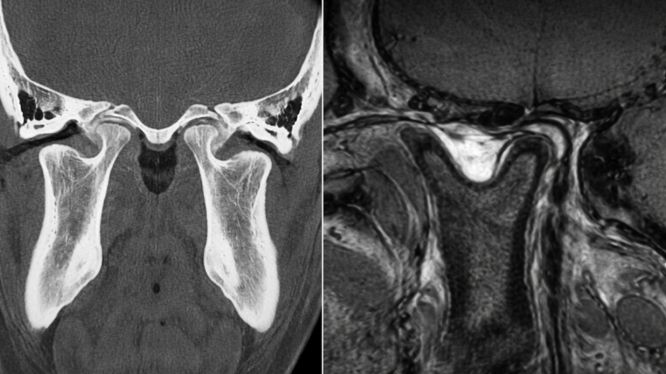

🧠 Tomografía ATM: visión tridimensional real

La tomografía atm permite obtener imágenes tridimensionales de la articulación.

A diferencia de la radiografía tradicional:

✔️ No hay superposición

✔️ Permite ver estructuras en cortes

✔️ Evalúa desgaste óseo con precisión

✔️ Detecta asimetrías mínimas

✔️ Mide desplazamientos

🔬 Cone Beam Dental para ATM: el estudio más preciso en odontología

El cone beam dental para atm es una tomografía de haz cónico especializada en estructuras maxilofaciales.

Es el estudio ideal cuando queremos evaluar:

🦴 Estructura ósea del cóndilo

🦴 Degeneración articular

🦴 Cambios por bruxismo

🦴 Desgaste

🦴 Asimetrías

🦴 Posición del cóndilo en reposo y en apertura

✔️ Imagen 3D de alta precisión

✔️ Menor radiación comparada con tomografías médicas convencionales

✔️ Cortes milimétricos

✔️ Diagnóstico más exacto